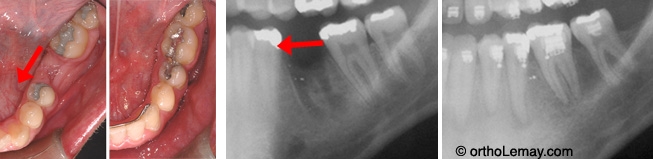

Molaire inférieure récemment extraite. Fermeture d’un espace d’extraction de 11 mm ce qui évite de faire remplacer cette molaire.